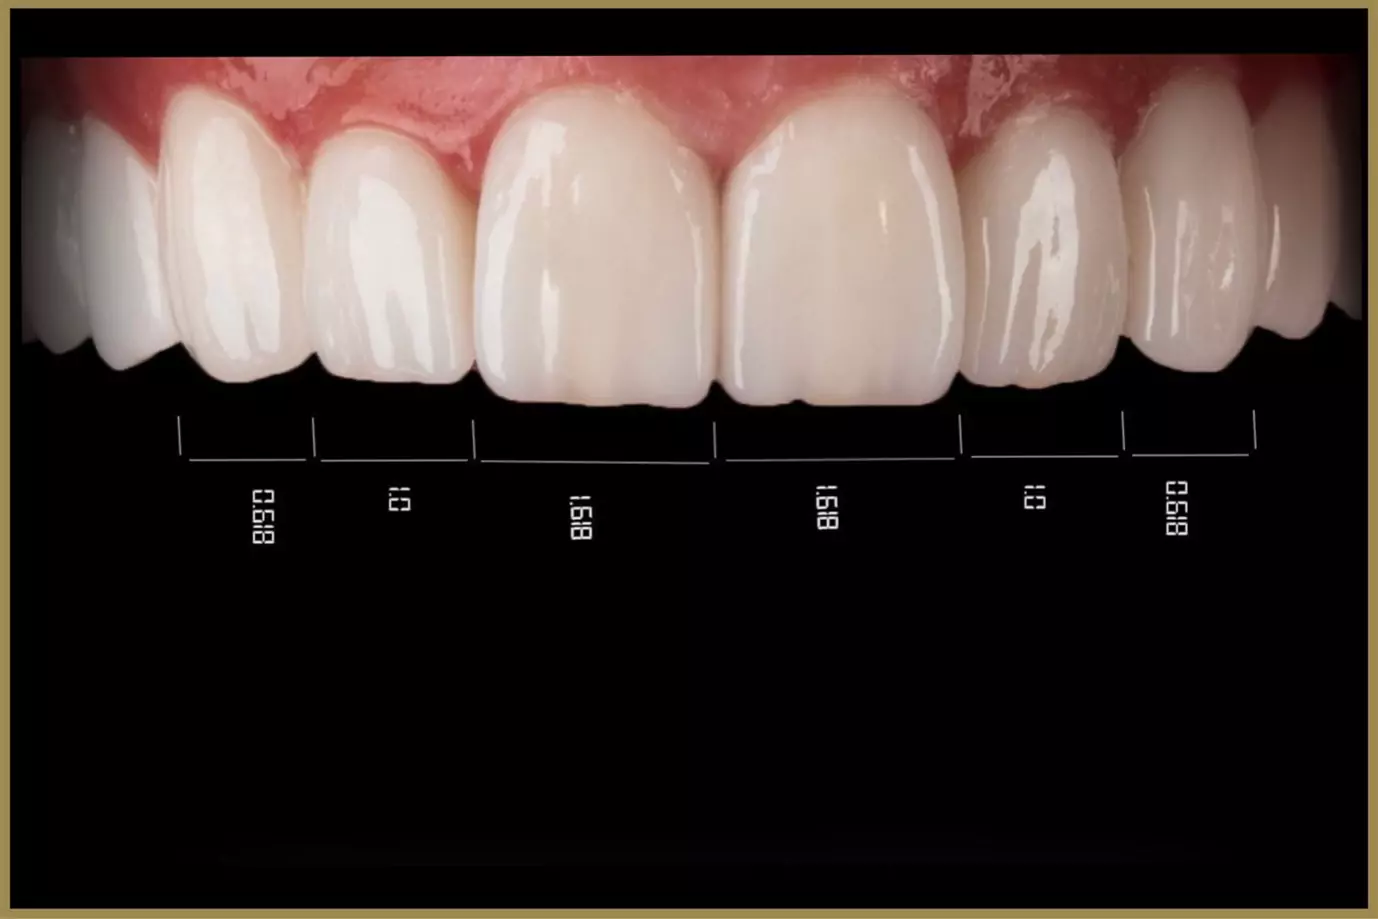

Digital X-rays, intraoral scanning, smile simulations, and computer-guided treatment planning.